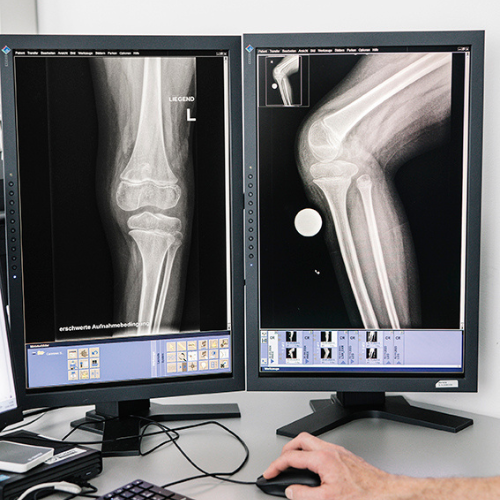

Untersuchungen zeigten rasch die Ursache. Eine Bandinstabilität und Überbeweglichkeit hatten zur Verschiebung der Kniescheiben geführt. Oberarzt Dr. Alexander Krebs, MSc, ist Leiter des Spezialteams Neuroorthopädie im Orthopädischen Spital Speising und in Sophias Behandlungsteam. „Normalerweise liegt die Kniescheibe vor dem Gelenk. Das ist für die Kniestreckung und Muskulatur wichtig. Bei der Patientin waren jedoch beide Kniescheiben seitlich verrutscht. Das führte dazu, dass das Knie keine aktive Streckfunktion hatte und die Kniestabilität nicht gegeben war. Deshalb konnte sie nicht gehen.“

Im Röntgen zeigt sich die Position von Sophias Kniescheiben.